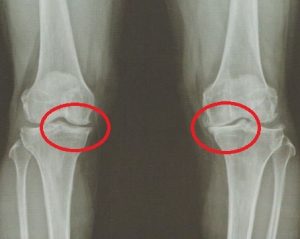

퇴행성 무릎 골관절염 (퇴행성 슬관절염) 안녕하세요. 고래한의원 박대명 원장입니다. 오늘은 중장년층에서 흔하게 나타나는 ‘퇴행성 무릎 골관절염’, 즉 ‘퇴행성 슬관절염’에 대해 말씀드리겠습니다. ‘퇴행성 무릎 골관절염(퇴행성 슬관절염)’은 이름 그대로 만성적이고 퇴행적인 변화로...

안양 고래한의원 - 퇴행성 무릎 골관절염001